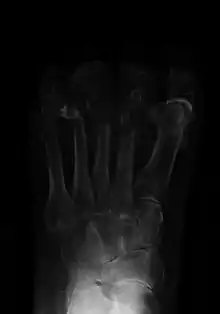

Radiographs and CT are the initial method of diagnosis, but are not sensitive and only moderately specific for the diagnosis. They can show the cortical destruction of advanced osteomyelitis, but can miss nascent or indolent diagnoses.[23]

Diagnosis of osteomyelitis is often based on radiologic results showing a lytic center with a ring of sclerosis.[13] Culture of material taken from a bone biopsy is needed to identify the specific pathogen;[26] alternative sampling methods such as needle puncture or surface swabs are easier to perform, but cannot be trusted to produce reliable results.[27][28]